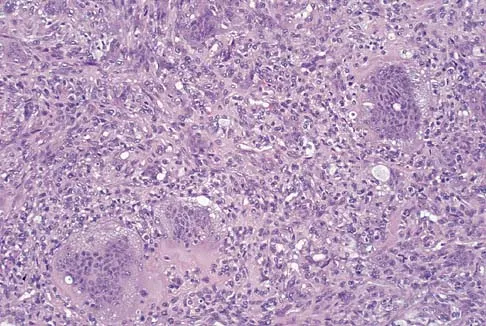

Question 74

A 10-year-old boy has a painful thigh mass. A radiograph, MRI scan, and biopsy specimen are shown in Figures 42a through 42c. What is the most likely diagnosis?

Explanation

A destructive mixed lytic and blastic metaphyseal lesion with a large soft-tissue mass in an adolescent is most likely an osteosarcoma until proven otherwise. The epicenter of the tumor is on the surface of the bone, most likely involves the periosteum, and is more likely to be chondroblastic in nature. Parosteal osteosarcoma is a low-grade tumor, much more radiodense, usually smaller, and found in the posterior distal femur of middle-aged patients. Chondrosarcomas are distinctly rare in childhood.